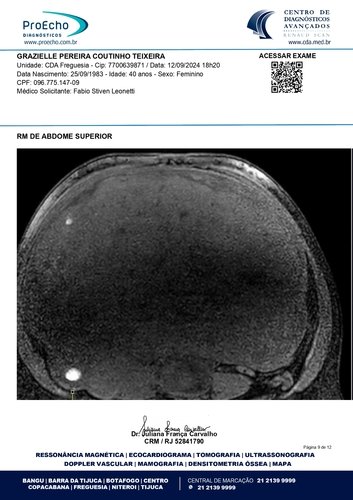

Olá, meu nome é Grazielle, tenho 41 anos e estou enfrentando a batalha mais difícil da minha vida. Fui diagnosticada com quatro miomas, sendo que o maior deles mede 30 x 20 x 28 cm e está comprimindo meus órgãos internos, além de endometriose, um cisto no ovário direito, mucocele de apêndice e um nódulo no intestino. Minha barriga está tão inchada que parece a de uma mulher grávida de 9 meses. Mas, apesar da aparência, o que mais preocupa os médicos é o apêndice inflamado. Se ele estourar, pode causar uma infecção generalizada e me levar a óbito. O tempo é curto: os médicos recomendaram que eu faça a cirurgia no máximo em três meses.

Abaixo, você encontrará os laudos médicos e imagens dos exames que comprovam o meu diagnóstico, bem como o orçamento detalhado da cirurgia. Se tiver alguma dúvida, estarei à disposição para fornecer mais informações.

Ressonância magnética: https://drive.google.com/file/d/1oSvors6sJRCRTZHVSZs9YeKzpw54SFw5/view?usp=sharing